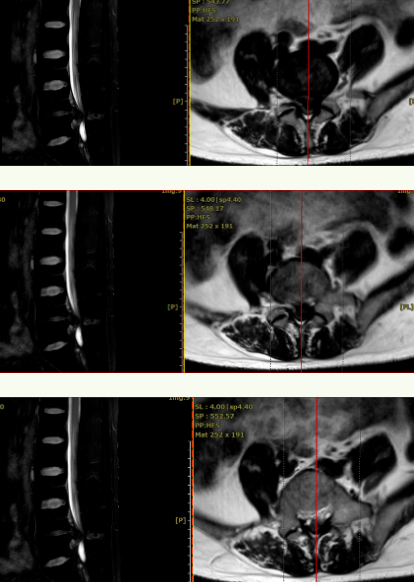

查体:扶拐跛行步态,起坐困难,脊柱轻度代偿性侧弯,腰4/5棘突及椎旁压痛、叩击痛明显,腰部活动受限。腰痛向左侧大腿后侧、小腿后外侧放射致足背,足背麻木感,较对侧感觉减退,踇趾背伸肌力4级,直推抬高实验30°阳性。术前影像:X线见:腰4/5椎间隙变窄,腰椎前凸变小,未见明显腰椎不稳定。

术前CT见:腰4/5椎间盘巨大凸出向后下方,左侧旁中央及侧隐窝狭窄明显,伴腰4、5椎体后缘钙化。

腰椎MRI见:腰4/5椎间盘变性,椎间盘巨大突出,硬膜囊受压明显,左侧椎间孔明显狭窄,左侧神经根受压明显。